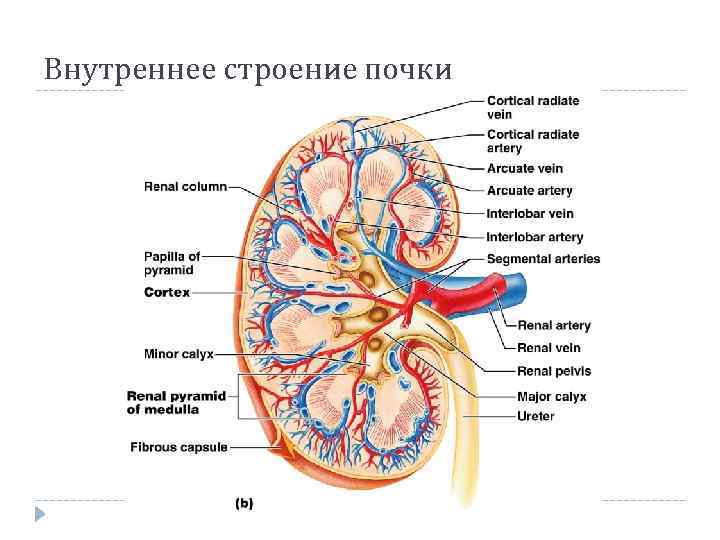

Внутреннее строение почки

Внутреннее строение почки

Внутреннее строение почки

Внутреннее строение почки